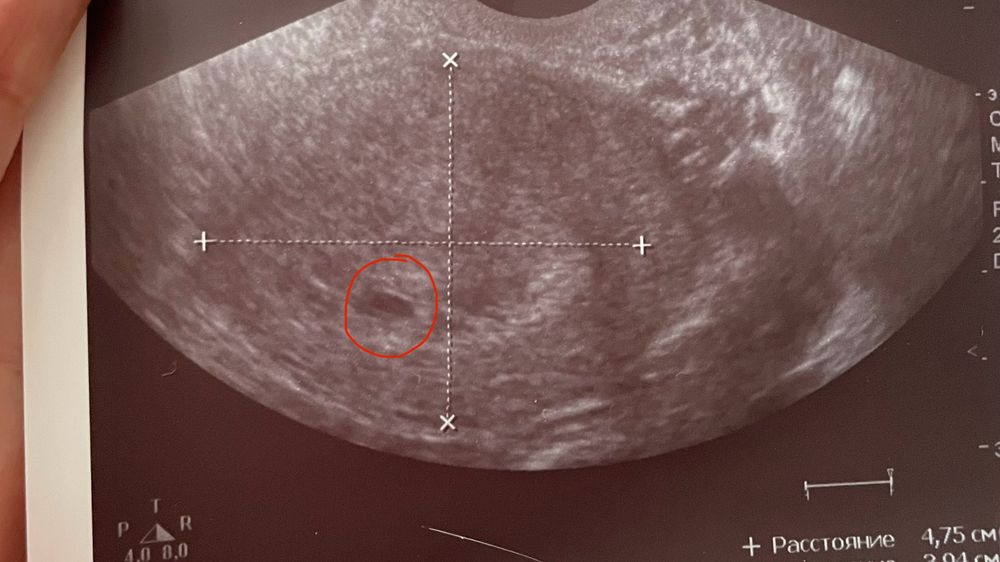

Изображение По моему оно и было 5 мм

Изображение тут пя-4мм